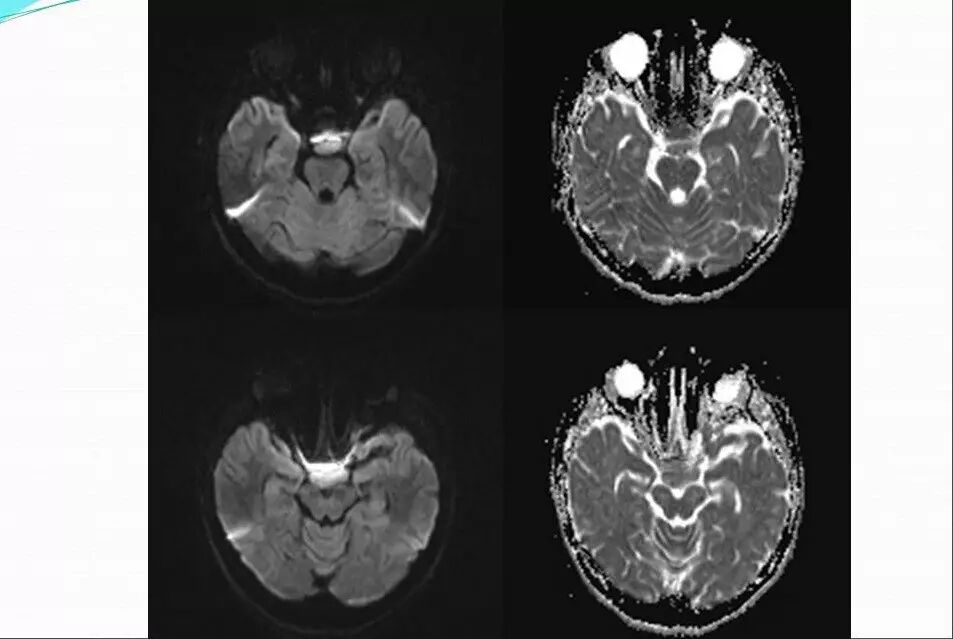

2.MR检查显示肿瘤位于鞍区,分叶状生长,呈稍长T2、稍长T1异常信号影,边界清楚,内部信号不均匀,其内可见“微囊”状异常信号影,视交叉受压上抬,DWI呈等或略高信号影,注药后呈不均匀明显强化;